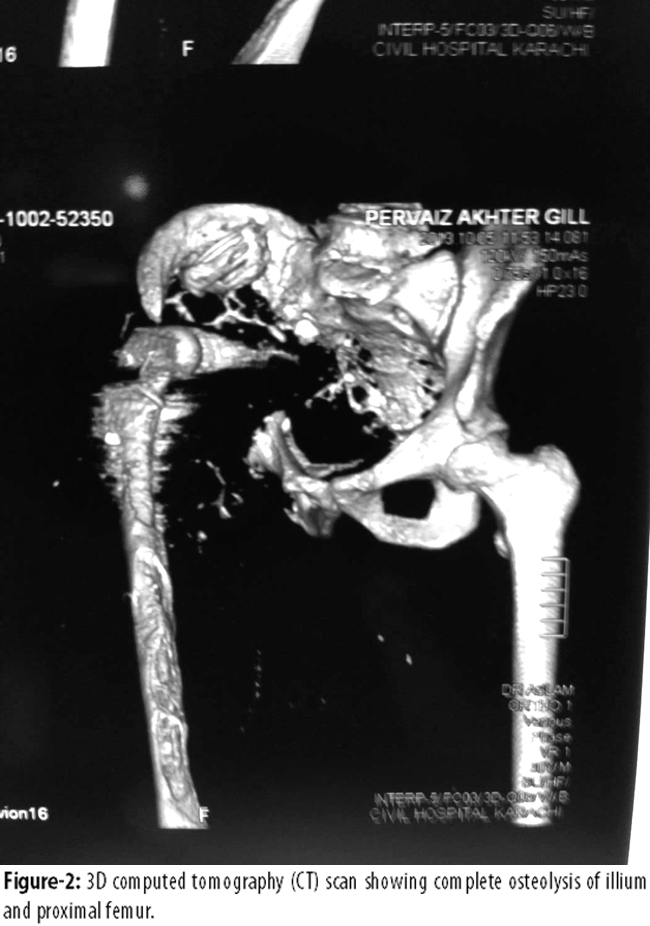

Radiologically, osteolysis was seen around the stem, illium was completely destroyed (Figure-1), medial side of femoral shaft was eroded (Figure-1 & 2),

Posterior view showing eroded illium (Figure-3)